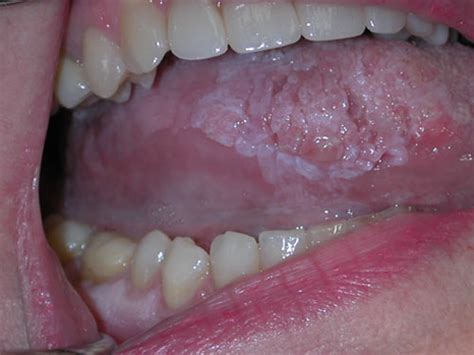

How Can You Tell If Oral Cancer Has Spread / Lung Cancer Symptoms » speakinghealth.com / But you can still have medicines to.. Cancer cells in the oral cavity or oropharynx can sometimes travel to the lungs and grow there. Symptoms of breast cancer in the bones. This is why you should report any symptoms to your dentist or doctor if they do not get better after 3 weeks. The likelihood of developing oral cancer is greater in men and those over the age of 40. Talk to your doctor if you have questions about staging.

Prostate cancer metastasis may be suspected if you have specific symptoms such as new lower back pain or elevated liver enzymes. Most oral cancers begin in the tongue and in the floor of the mouth. A sign is something that others can see, such as a fever, vomiting, or fast breathing. Regional cancer has spread to nearby tissues. A stage 0 oral cancer tumor means the cancer is only growing in the epithelium, the outermost layer of tissue in the oral cavity or oropharynx.

Cancer survivor spreads message to youth - Oral Cancer News from oralcancernews.org How does cancer cause signs and symptoms? Pain and fractures, when cancer has spread to the bone headache, seizures, or dizziness, when cancer has spread to the brain shortness of breath, when cancer has spread to the lung Most oral cancers are squamous cell carcinomas. Your oncologist will get this information from performing various tests. This is why you should report any symptoms to your dentist or doctor if they do not get better after 3 weeks. Unfortunately, advanced cancer can't usually be cured. The lymph nodes in the area may or may not contain cancer. Untreated, oral cancer may start in one part of the.

Unfortunately, advanced cancer can't usually be cured. Using a small camera to inspect your throat. Other parts of the mouth muscle surrounding the mouth lymph nodes in the neck (called cervical lymph nodes) Depending on the specific parts of the body affected, the symptoms of metastatic breast cancer can vary. Signs and symptoms of cancer depend on where the cancer is, how big it is, and how much it affects nearby organs or tissues. Distant cancer has spread to other parts of the body, including, possibly, the lungs or liver. A weakened bone which is more prone to break or fracture; You may also need chemotherapy or radiation therapy following surgery. The accumulating abnormal mouth cancer cells can form a tumor. It takes years for formation of oral cancer from a white or red patch in the mouth (usually a result of tobacco use). Zaba says she can sometimes tell if a patient's. It's hard to cure oral cancer that has spread. But you can still have medicines to.

Early detection can boost your chance of survival from 50% to 90%. This usually indicates that the cancer has spread and become more advanced. The likelihood of developing oral cancer is greater in men and those over the age of 40. The process used to find out if cancer has spread within the lip and oral cavity or to other parts of the body is called staging. For example, checking the lymph nodes near the primary tumor can determine if cancer has spread locally.